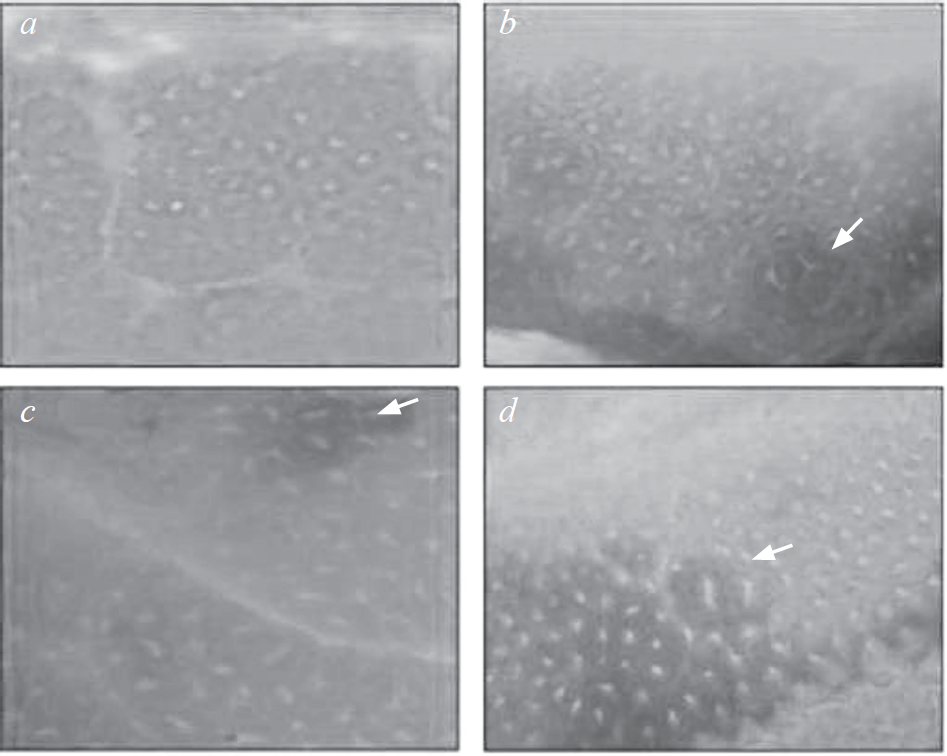

В среднем масса животных по группам к моменту выведения из эксперимента достоверно не отличалась и составляла в среднем 22 г. Как следует из полученных результатов (см. табл. 2), частота ФАК была наиболее высокой в группе животных, получавших как МНМ, так и L-тироксин. Было выявлено достоверное отличие по отношению ко всем исследуемым группам: по отношению к группам 1, 3, 4, 5 и 6 при р < 0,001, тогда как по отношению к группе 2, животные которой получали только МНМ, различия были зарегистрированы и значимы при р < 0,01. При этом группа контроля и группа, которая получала антигормональный препарат, не отличались достоверно по частоте возникновения ФАК. Интересно отметить, что группа, которая получала МНМ и ПТУ, также достоверно не отличалась по частоте ФАК от группы, получавшей только гормональный препарат. Причем у отдельных животных первой, контрольной группы, которые не получали никаких субстанций, также присутствовали единичные ФАК в слизистой оболочке прямой кишки (рис. 2). Такие же наблюдения были сделаны для остальных групп мышей. Напротив, в слизистой прямой кишки у ряда мышей из группы 3 в единичных случаях регистрировались множественные ФАК (рис. 3). Как правило, размер ФАК варьировал в пределах 0,1–0,3 мм.

Рис. 2. Фокусы аберрантных крипт в слизистой прямой кишки: а — нормальная слизистая; b, c, d — фокусы аберрантных крипт указаны стрелками. Увеличение ×400

Fig. 2. Foci of aberrant crypts in rectal mucosa: а – normal rectal mucosa; b, c, d – foci of aberrant crypts indicated by arrows. Magnification ×400